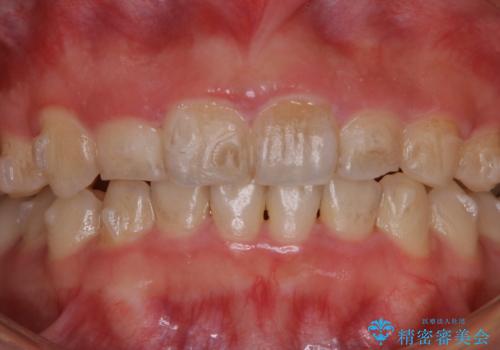

- インビザラインでのマウスピース矯正中の方で、歯の表面のステインをきれいに取りたいとのことでした。PMTC60分コースを行いました。

PMTC(保険外治療)は、毎日の歯磨きで落としきれない汚れや、コーヒ、紅茶・タバコのヤニなどの着色も除去します。目には見えない歯と歯の間・歯肉の境目・インビザライン中はアタッチメント周囲などに残っているプラーク(歯垢)もしっかり取り除きます。PMTCでは専門的な機械や材料を使用して、徹底的に汚れを除去するため、虫歯・歯周病・口臭予防などにつながります。

またPMTCを行うことで、ご自身本来の歯の色になり自然な明るさになります。